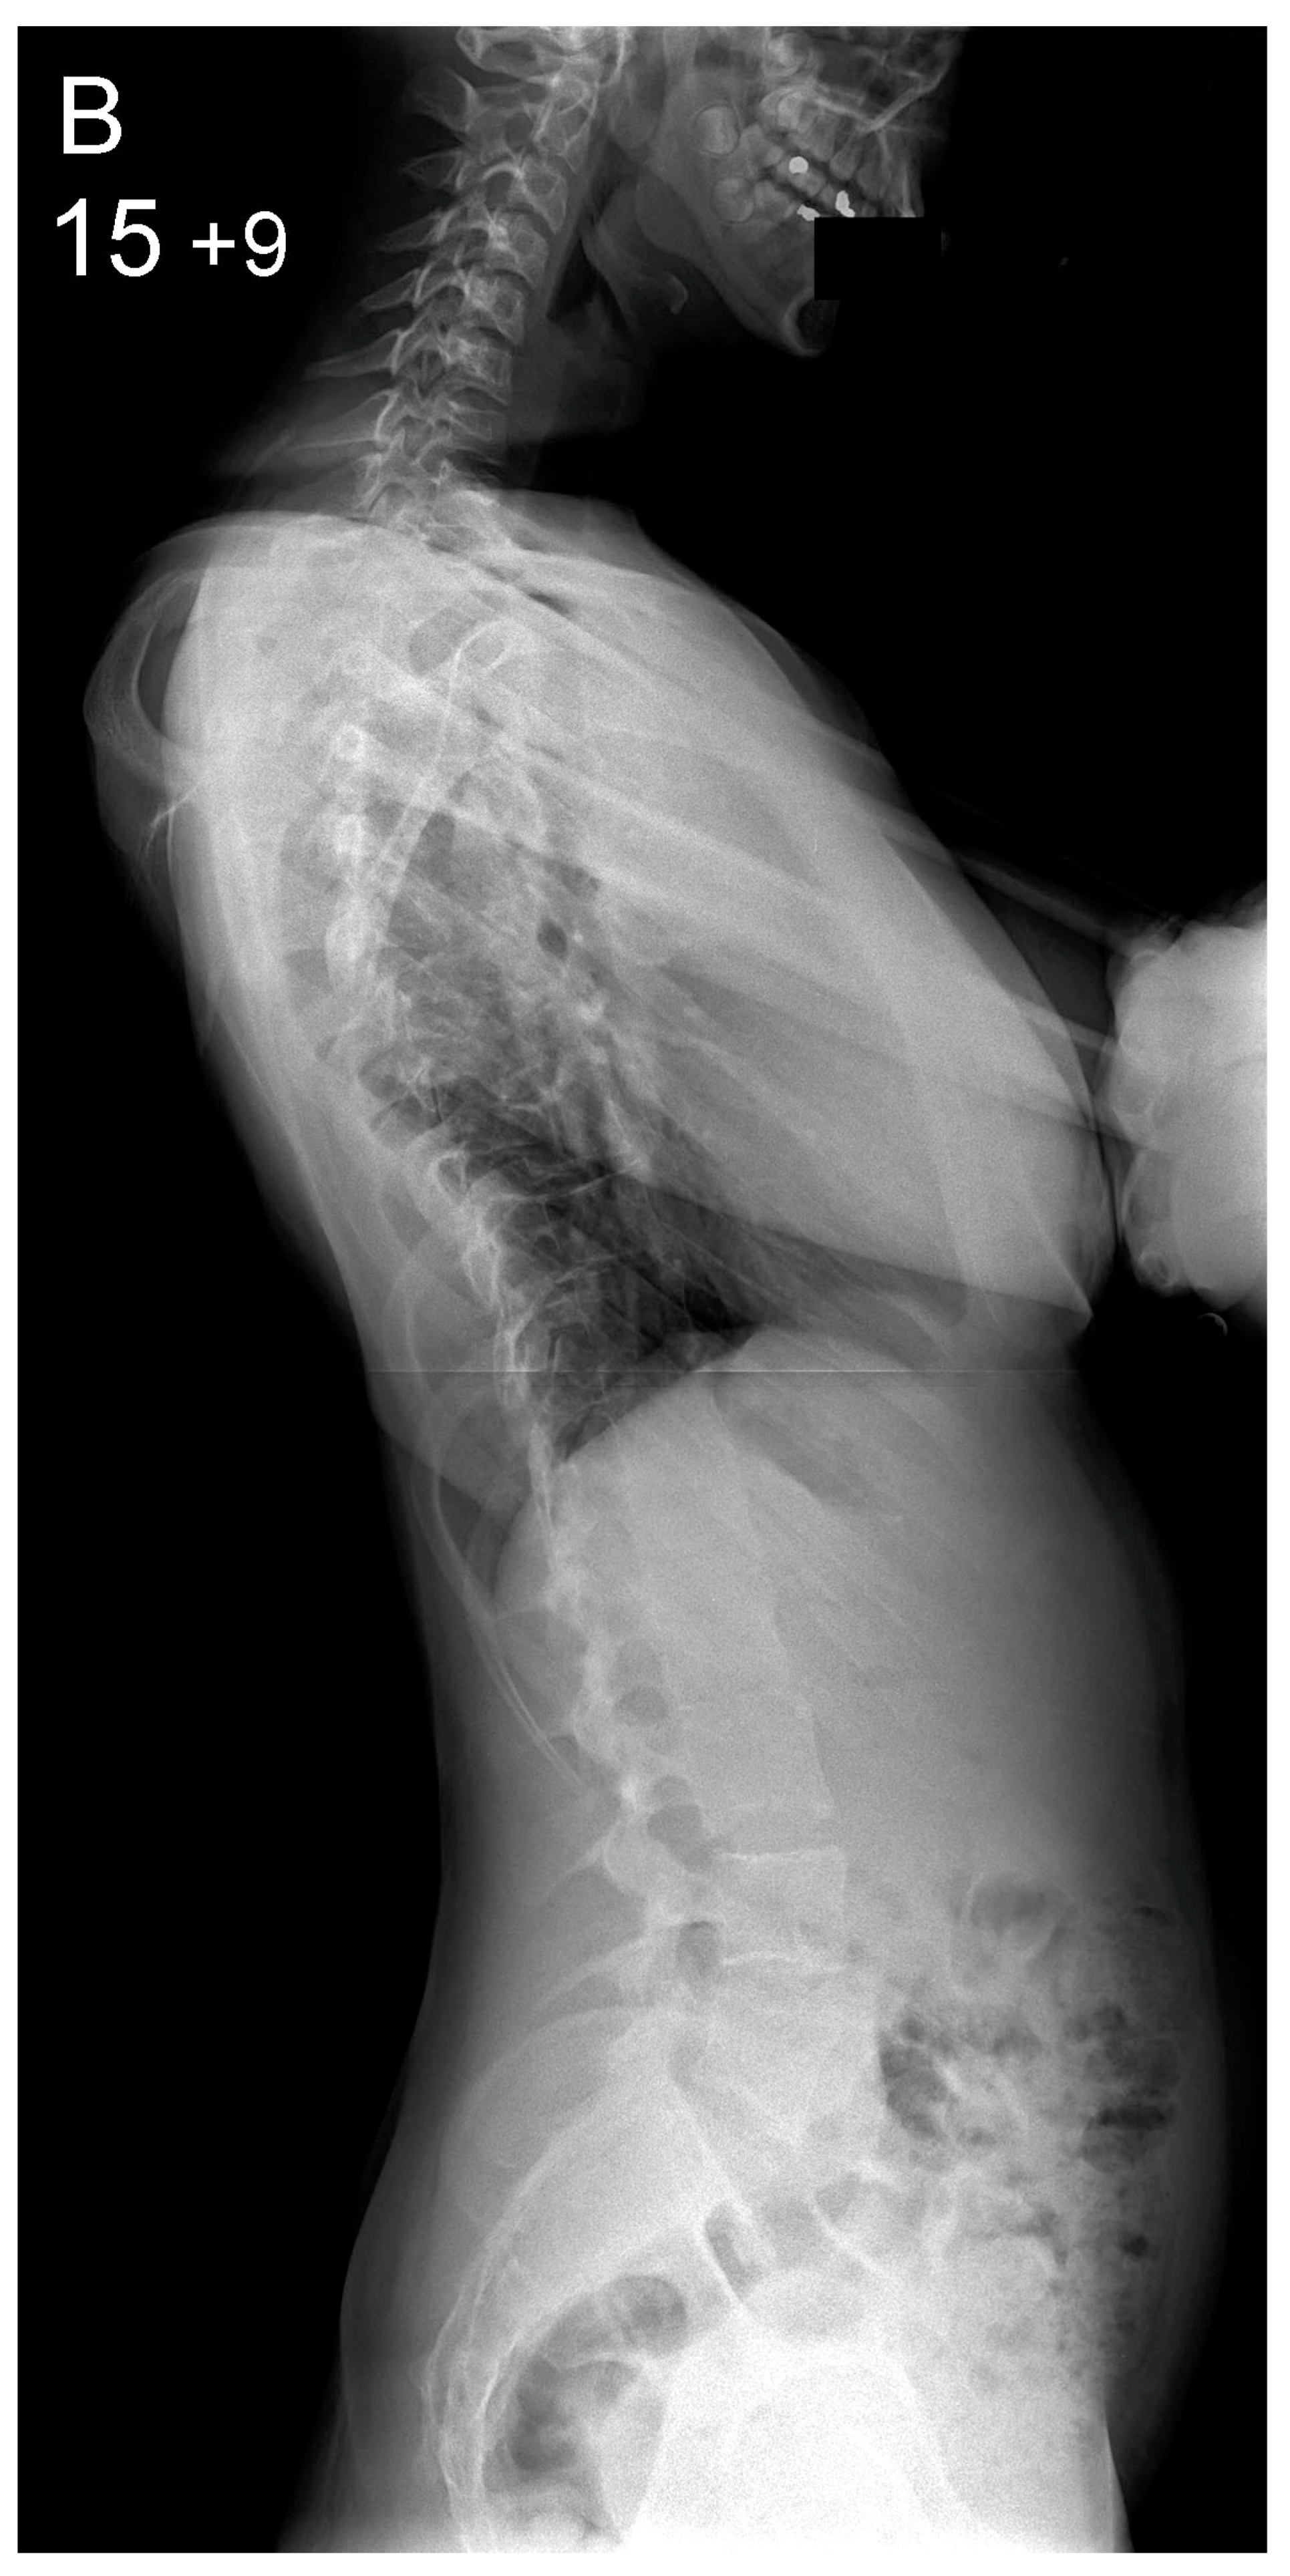

Figure 2.

Patient aged 15 years and 9 months with a right thoracic AIS producing thoracic translocation and listing of the trunk to the right, as well as a lordotic thoracic spine causing spinal penetration into the chest, partial bronchial obstruction and right lower lobe atelectasis (A,B). The patient underwent posterior scoliosis correction using the HS technique which restored segmental and global coronal/sagittal spinal balance at latest follow-up (age 19 years and 2 months) into adult life (C,D). Clinical photographs demonstrate excellent correction of the coronal deformity and associated rib hump after scoliosis surgery (E–H).